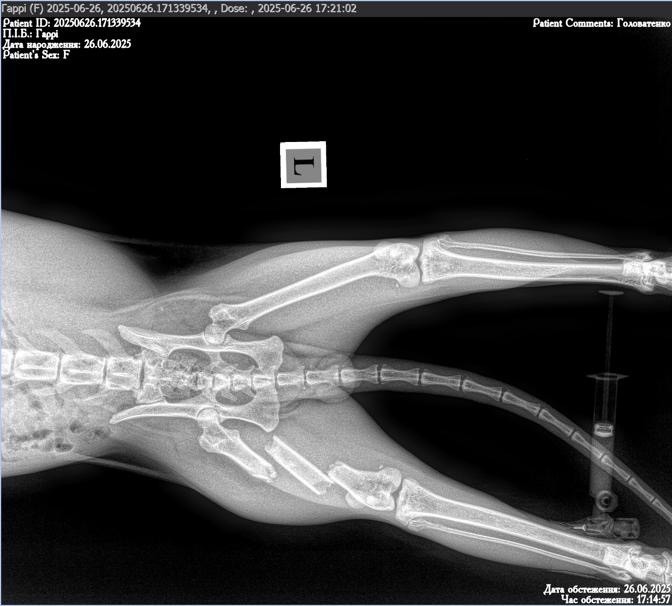

Then one day, Gary suddenly appeared dragging a completely shattered leg behind him - and then disappeared again. We tried to find him day in and day out, and when we did, he was so weak that crows were circling around him. We assume that Gary was hit by a car, which left him with multiple fractures.

In June, Gary underwent major surgery at VetFamily veterinary clinic to repair his injury, which the vets described as horrific. His leg was stabilized with external fixators, and he remained in in-patient care at Cat+Vet clinic for two months. Recently, we were able to move him into foster care so he could continue recovering in a calmer environment.

During his first week in foster, it became clear that something had gone wrong with the fixators. We rushed him to ArtVet clinic, where it was confirmed that the fixators had failed and had to be removed. Gary underwent another emergency surgery and is now recovering in a small crate to limit his movement as much as possible. At this stage, we still don’t know whether he will be able to keep his leg, but we are doing everything we can to support his recovery and ensure he receives the best care possible.

To give a clear picture of his injury and current condition, we’ve included two videos at the end. Please note that while there is no blood or gore, the first video shows his broken leg and the second shows the fixators, which some may find disturbing.